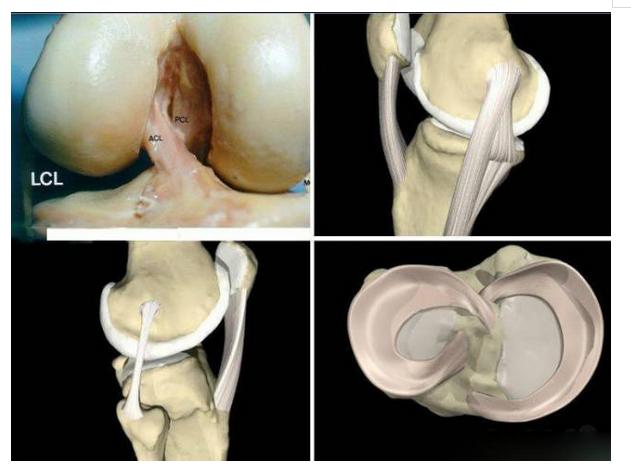

14、半月板损伤

发生于膝关节突然旋转损伤,如跑步者突然改变方向,也可发生于慢性退变过程中,尤其是有膝关节不稳定时,反复膝关节疼痛,交锁时加重,下蹲或膝关节旋转时可引发交锁,轻度积液,关节线压痛,股内侧肌萎缩, McMurray试验阳性 (阴性不能排除诊断)X线平片阴性。